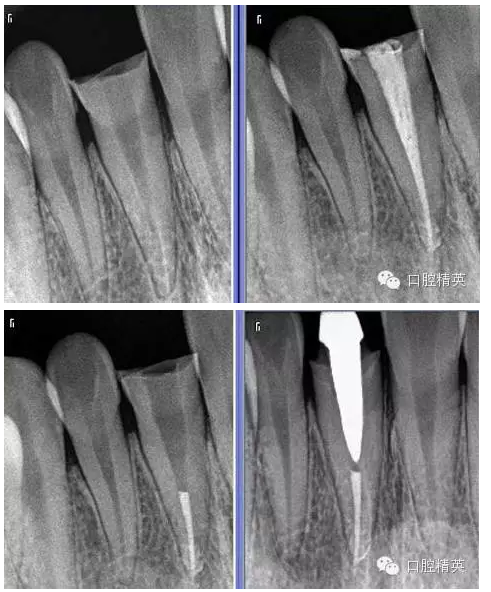

6:術(shù)前后的X-RAY。

術(shù)前 ↑

術(shù)后 ↓